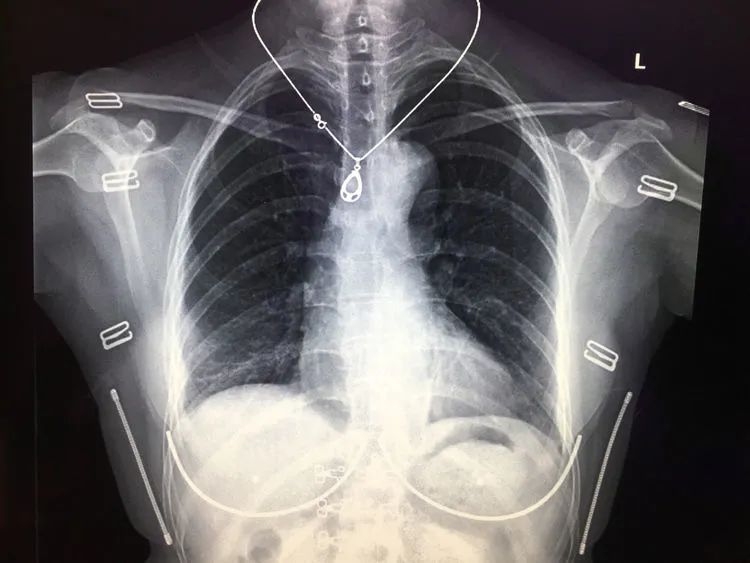

存在体表金属异物的胸部正位平片,图片来自镇安县医院影像科

部分女性内衣以及带金属的拉链、金属扣的衣物都会影响拍摄效果,拍摄前医生会要求尽量把这类衣物脱掉。

首饰类如金属项链、玉石挂件也需要摘掉。

衣服上带有钻、鳞片、塑料印花、金属装饰都会影响效果,金属扣子、拉链、打火机、硬币、工作牌等也是需要移除的重点物品。另外,皮肤若黏有药膏要清理干净。